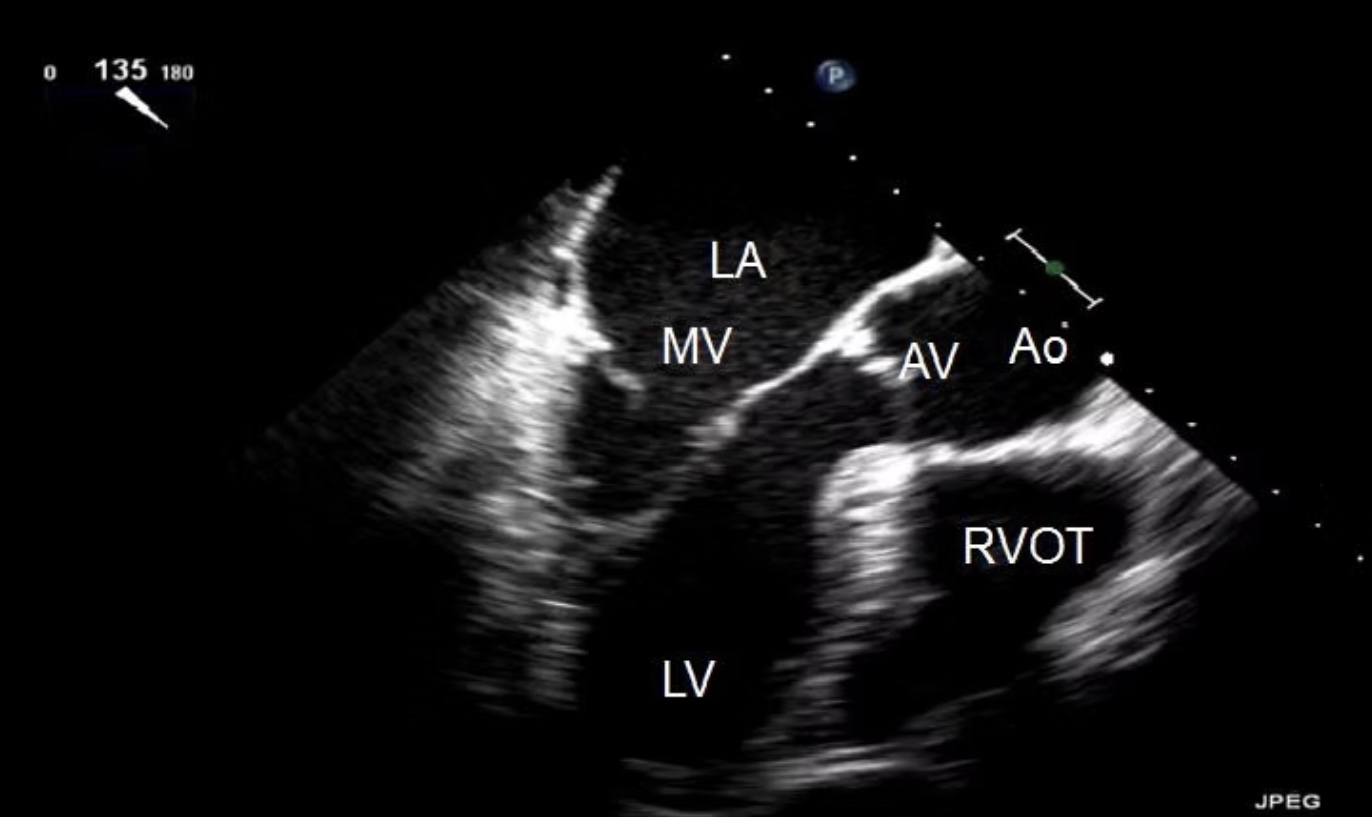

Identify the view and structures

ME AV LAX